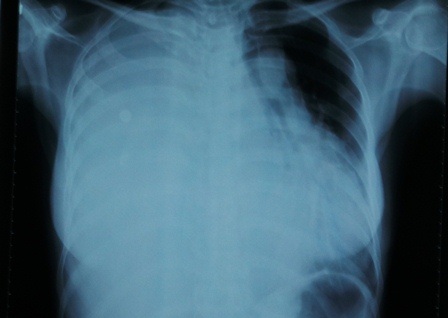

Sau lần vượt cạn thành công vào tháng 10/2013, sức khỏe của chị P. xuống dốc trông thấy. Chị thường xuyên có biểu hiện tức ngực, khó thở, phát âm không rõ tiếng… nên đến bệnh viện Chợ Rẫy kiểm tra, qua thăm khám lâm sàng và chẩn đoán hình ảnh bác sĩ “ngỡ ngàng” phát hiện khối u lớn chiếm trọn lồng ngực bệnh nhân, đè xẹp phổi phải, chèn ép và xô lệch tim.

Sau hơn một tháng chuẩn bị, cùng với sự quyết tâm của người bệnh, ngay 17/4 bệnh viện Chợ Rẫy quyết định thực hiện cuộc phẫu thuật cho bệnh nhân. Các bác sĩ đã phải chẻ xương ức, mở lồng ngực để bóc trọn khối u. “Quá trình lấy khối u ra ngoài gặp rất nhiều khó khăn do cục u rắn chắc lại dính vào cơ hoành, màng tim, các mạch máu chính trong lồng ngực và thành ngực, đè bẹp cấu trúc khác trong lồng ngực. Phải cần đến 4 bác sĩ vừa “nạy” vừa “kéo” chúng tôi mới bóc được khối u có trọng lượng lên tới 4,5kg, kích thước 30 x 75 x 25cm ra ngoài”, BS Vĩnh cho biết.